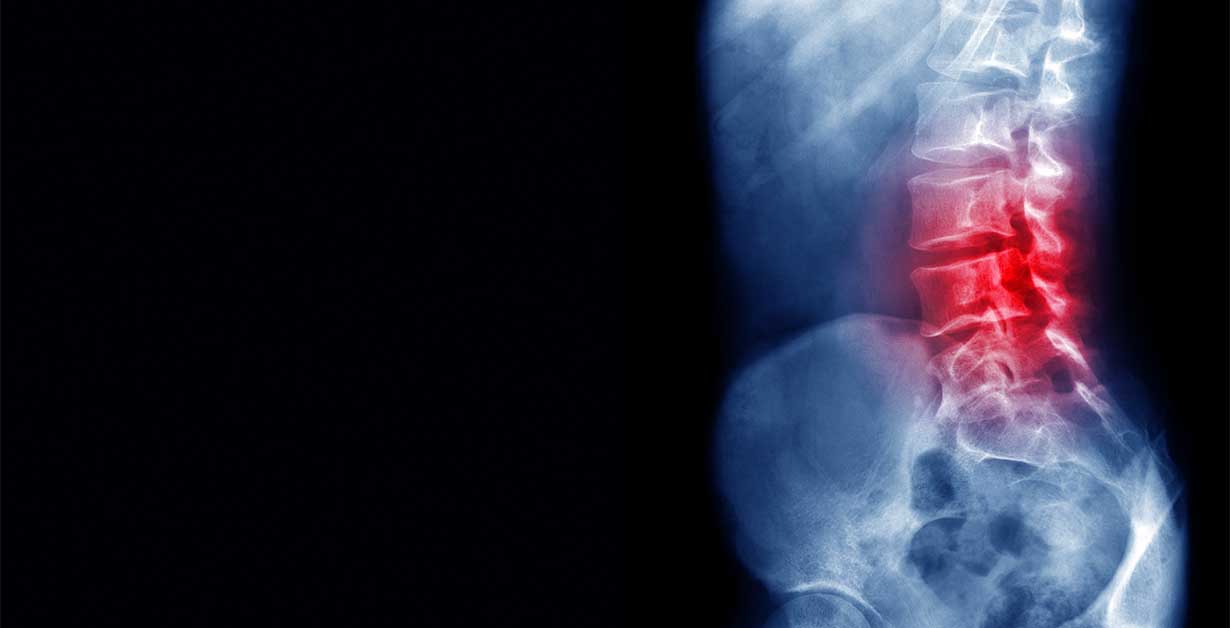

Durch diese Anheftung steht der untere Abschnitt des Rückenmarks, der Conus medullaris ungewöhnlich tief (sog. Konustiefstand). Durch den damit verbundenen Zug auf dem Rückenmark können neurologische Störungen auftreten.